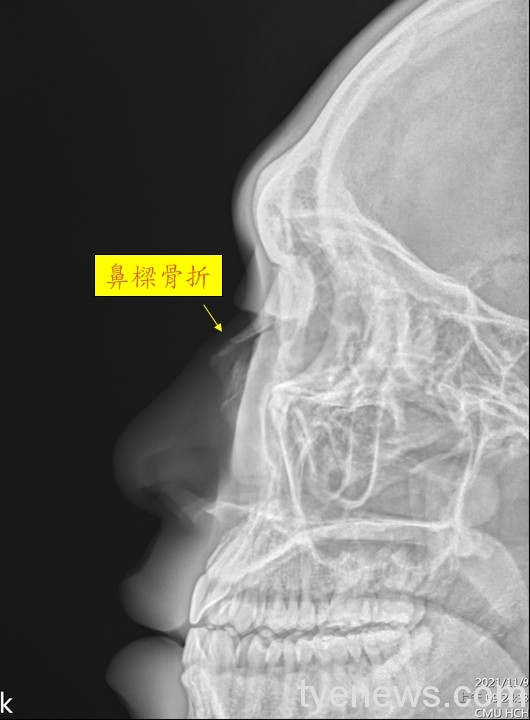

28 歲型男運動員小張(化名),球場上表現精湛,一次激烈對抗,鼻樑被對方球員撞歪,被送往中國醫藥大學新竹附設醫院急診就醫,經由X光檢查發現鼻骨骨折斷裂,鼻背明顯歪向右側,耳鼻喉科醫師蔡以璿診斷,因為骨折處嚴重腫脹不適合立即手術,經過兩天冰敷之後,腫脹處逐漸消退,施行微創閉合復位手術,手術約一小時,隔天即出院,術後骨折處用鼻外固定板固定一週,休養一個月後,小張恢復正鼻重建型男形象,又可重新回到球場上一展球技。

28 歲型男運動員小張(化名),鼻樑被對方球員撞歪,被送往中國醫藥大學新竹附設醫院急診就醫,經由X光檢查發現鼻骨骨折斷裂,鼻背明顯歪向右側。圖:中醫大新竹附醫提供